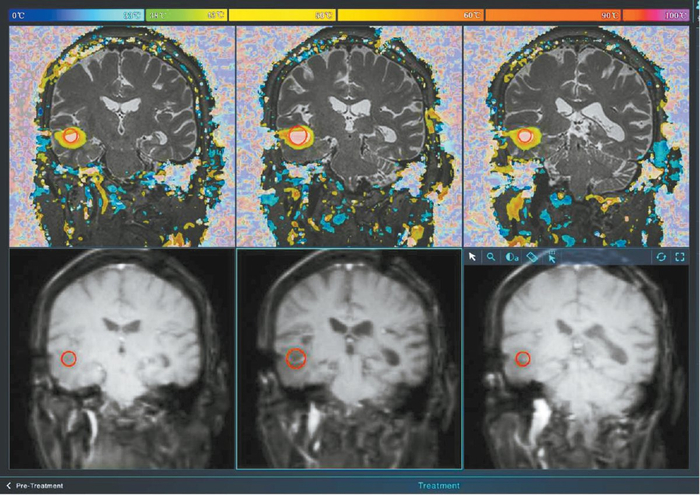

“利特刀”对患者脑部病灶实现精准消融,实际消融区域与预期完全一致。

神经外科手术导航机器人与“利特刀”牵手,根据前期手术路径的规划,医生将一根直径仅1.8毫米的激光光纤准确送到病灶中央,利用光热效应把预消融的区域温度提升到预定范围,病灶组织或者肿瘤在几分钟内即可被灭活。设备的温控精度在1摄氏度以内,操作精度则可达到亚毫米级,全流程的智能化、可视化,让机器人从“好帮手”升级成为“治疗师”。

“交卷”的时刻到了。手术的效果究竟如何,要回答这个问题,需要再对杜女士进行一次磁共振检测,观察病灶区域的实际情况。“别看这短短的10分钟,每一秒都是忐忑和煎熬。”刘文博说,当检查结果传回,所有人都松了一口气——实际消融的区域与预计完全一致,手术十分成功!